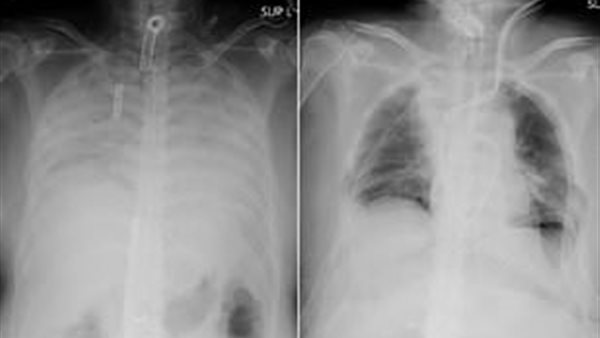

أجرى الأطباء في اليابان أول عملية زرع رئة في العالم من متبرع حي على لمريض يعاني من تلف رئوي شديد بسبب إصابته بفيروس كورونا الحاد.

زرع الأطباء أنسجة من رئتي زوجها وابنها السليمتين لاستبدال أجزاء من رئتي المريض الفاشلتين، حيث في حالة الزراعة من متبرع حي ، يلزم وجود متبرعين اثنين.

لكن مستشفى كيوتو قال إنها نجحت في أول عملية زرع أنسجة رئوية في العالم من متبرعين أحياء لمريض كوفيد -19 مصاب بتلف في الرئة.